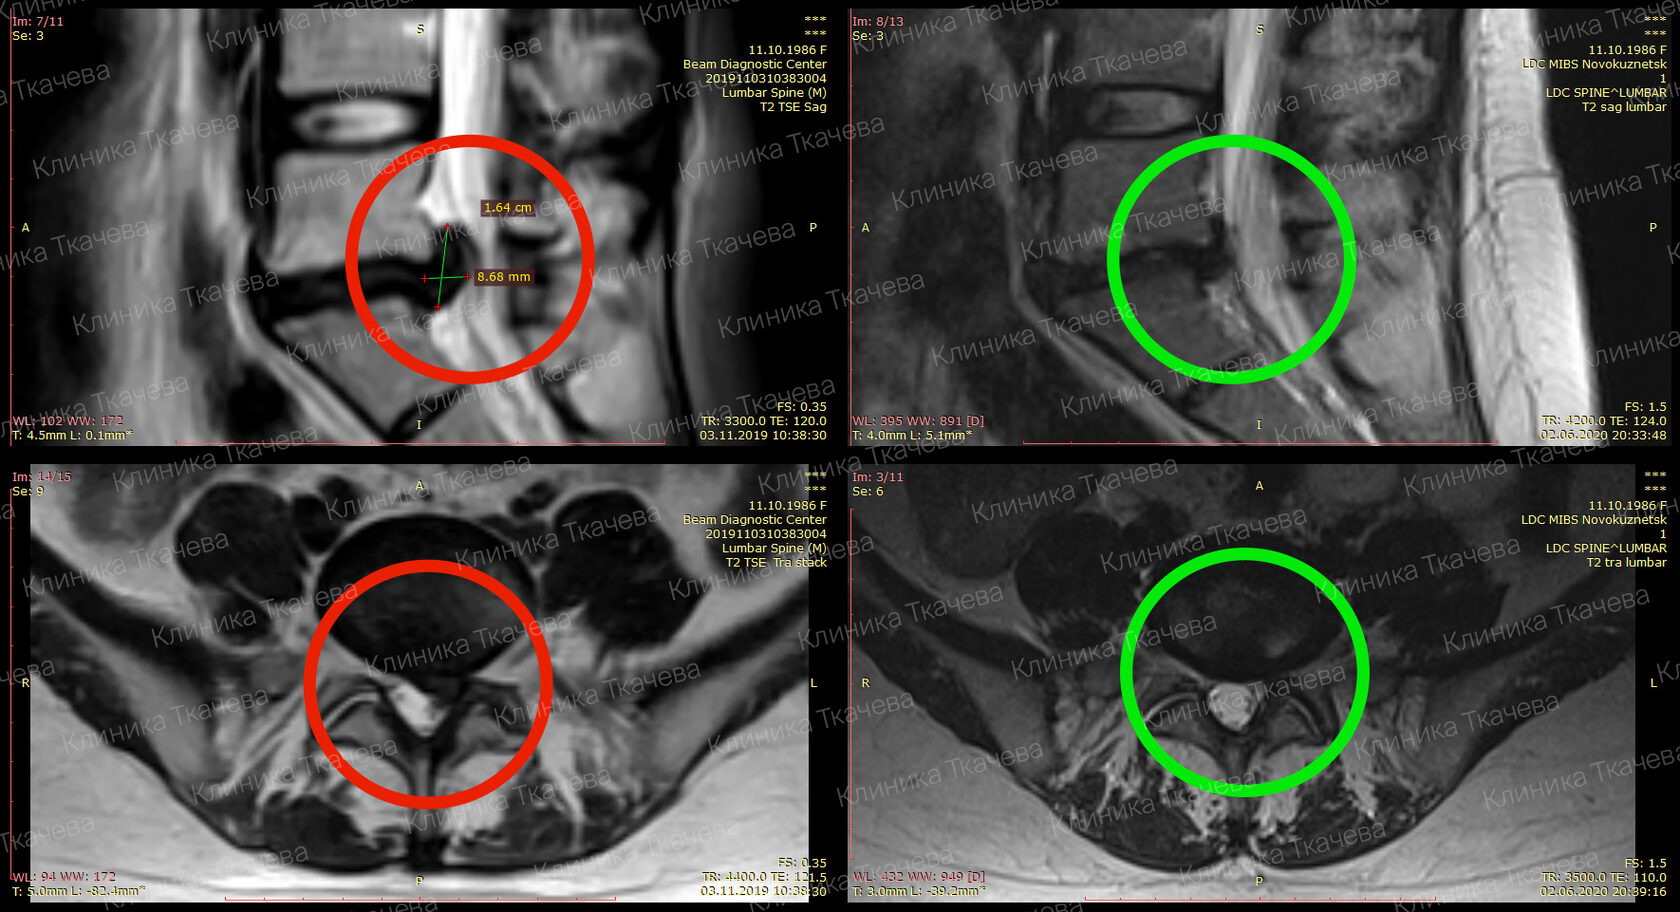

Грыжа Диска L5 S1 Фото

Грыжа Диска L5 S1 Фото 108 фотографий